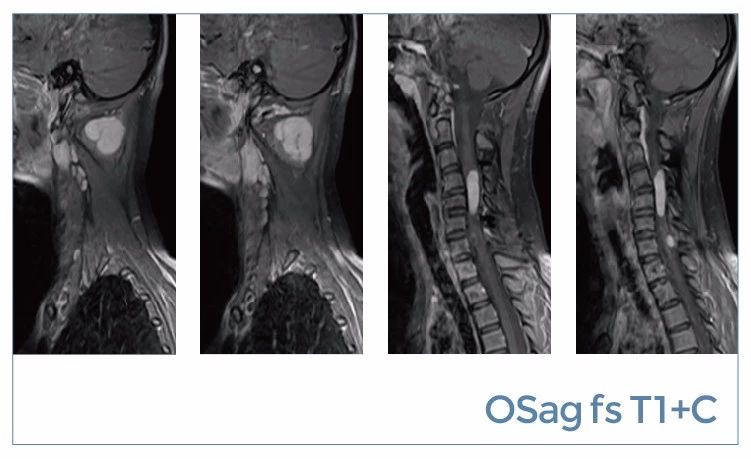

【朗润影像档案】20190816磁共振影像病例结果讨论